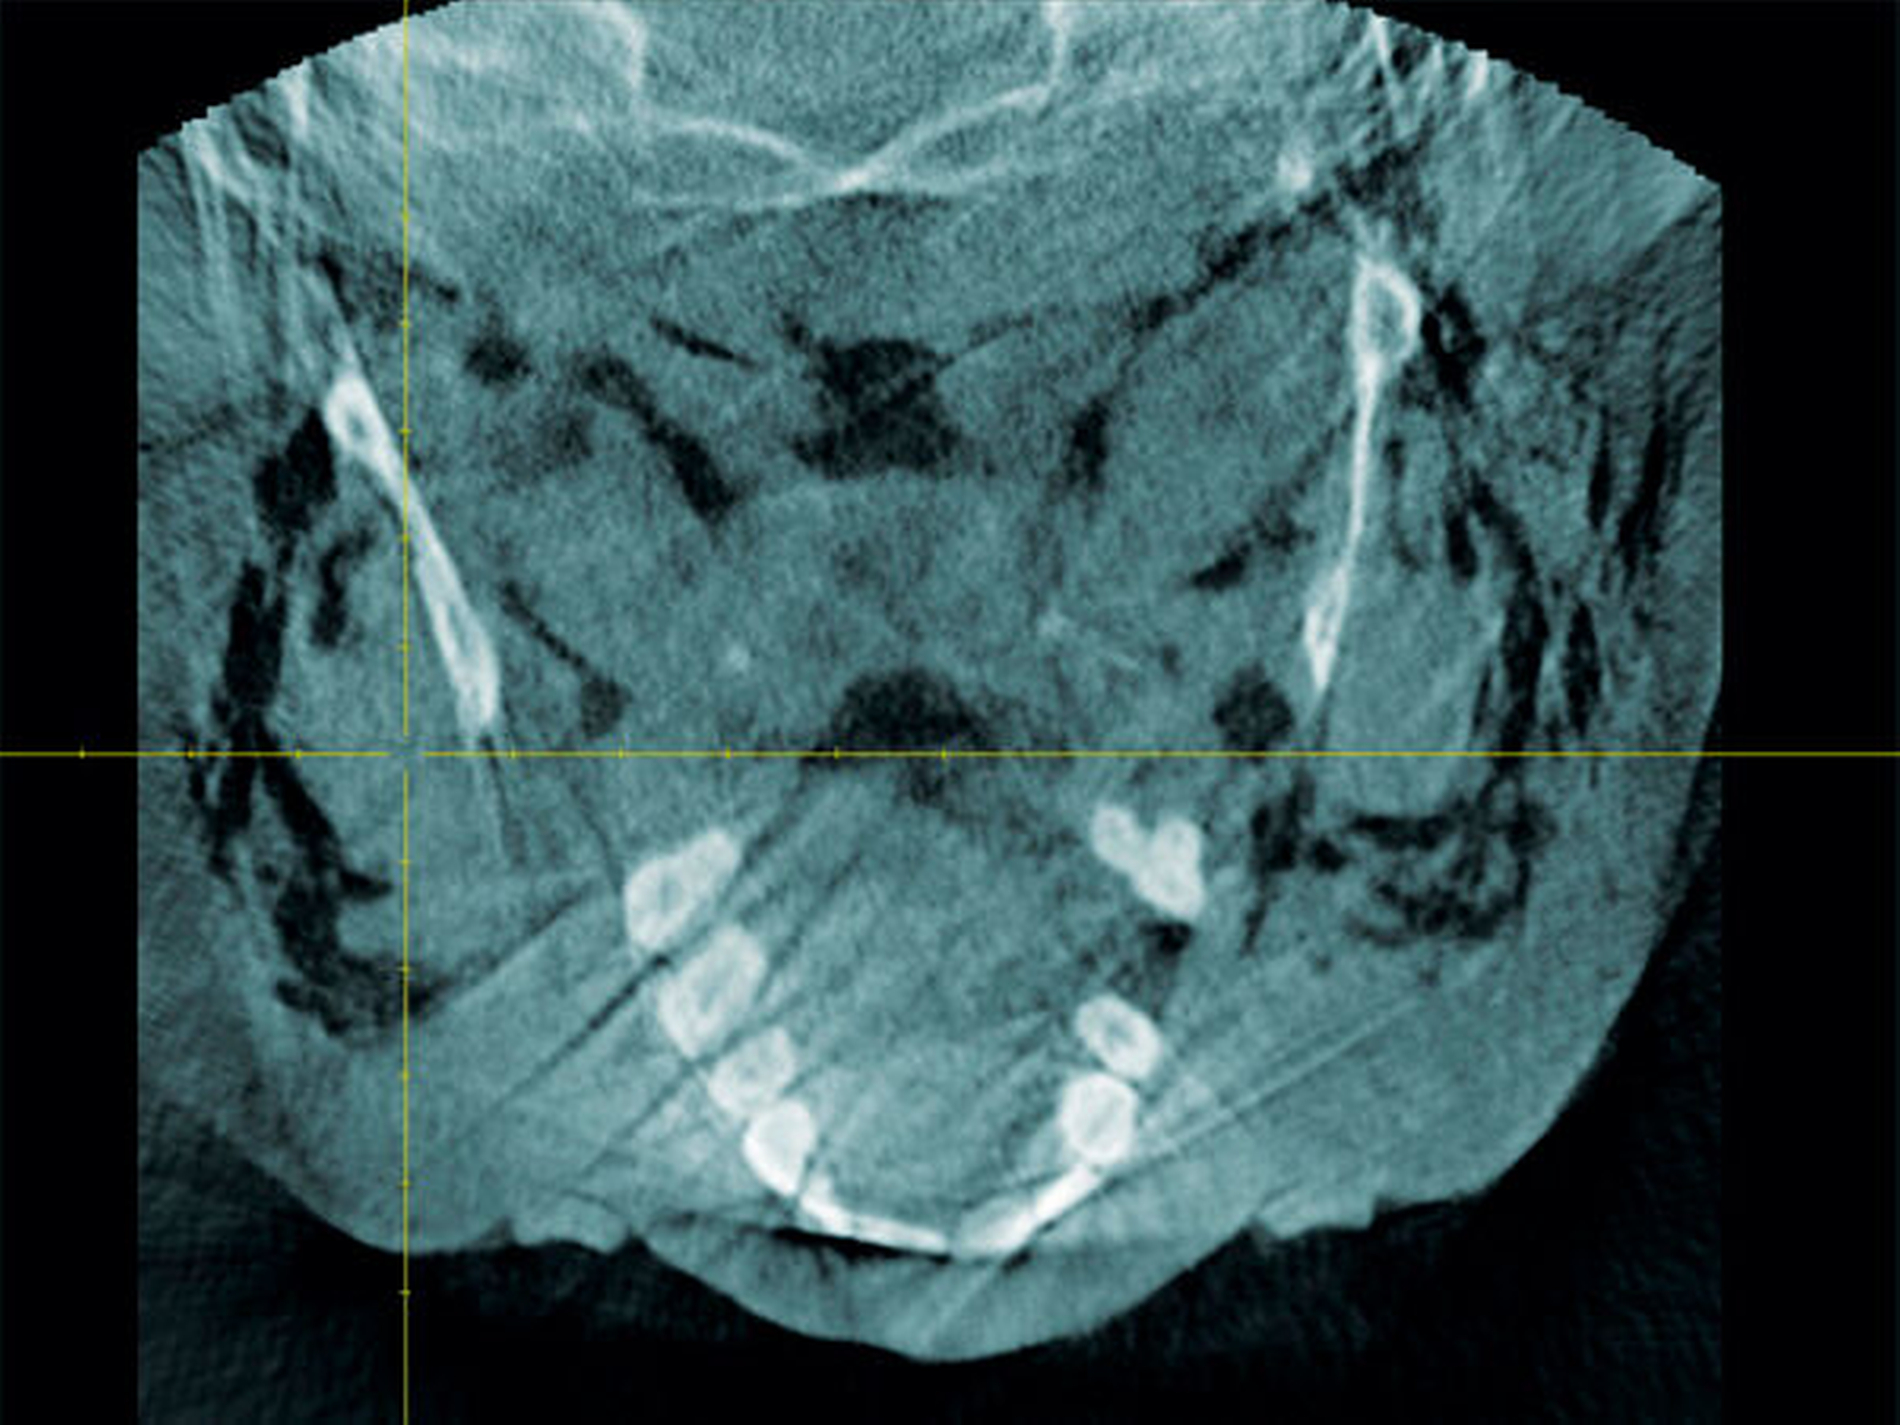

Zum Ausschluss einer Mittelgesichtsfraktur bei palpatorischem Weichteilemphysem erfolgte zur weiteren Diagnostik eine DVT-Aufnahme. Es zeigten sich keine Frakturen im Bereich des Mittelgesichts oder der Kiefer. Jedoch kam in der DVT-Bildgebung sowie in der OPT-Optik ein massives Weichgewebeemphysem zur Darstellung (Abbildungen 2 bis 5).

Weiterhin wird deutlich, dass bei in aller Regel doch sehr eingeschränkter Beurteilbarkeit von Weichgewebe im DVT in diesem speziellen Fall eine weiterführende Diagnostik und Therapie eingeleitet werden konnte.

Das Emphysem war initial im DVT so eindrucksvoll sichtbar, dass es trotz fehlender klinischer Symptomatik im Thoraxbereich, schwieriger Anamnese und blander zweidimensionaler Bildgebung der Lunge (RÖ-Thorax) der Faktor für eine weitere dreidimensionale Bildgebung (CT-Thorax) war, die letztendlich die Verdachtsdiagnose sicherte.

Zur Frakturdiagnostik im Mittelgesichtsbereich eignet sich das DVT sehr gut, außerdem ist die freie Luft des Emphysems im undifferenzierten Weichgewebe gut darstellbar.

Mittels der digitalen Volumentomografie können Weichteile schlecht bis gar nicht beurteilt werden, Lufteinschlüsse im Weichgewebe hingegen können gut dargestellt werden.